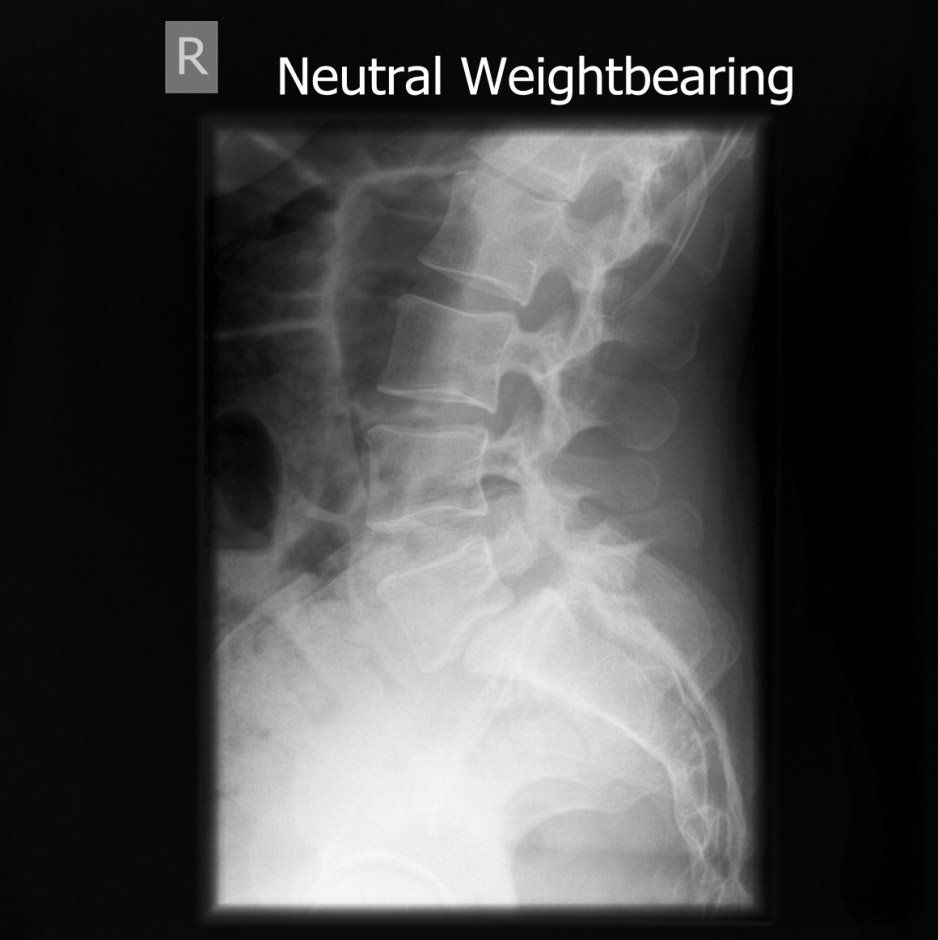

This is the before surgery X-ray showing that the lowest bone has slipped forward.